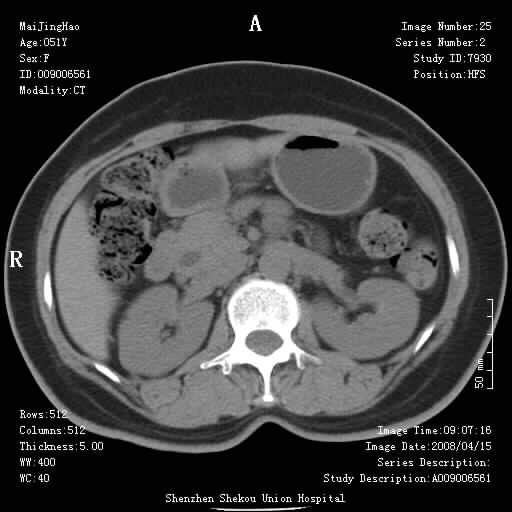

以下是引用liangshusheng在2008-4-26 12:34:00的发言:[br]11年前做的手术现在还有积气,可能吗?还是考虑有胆管炎产气,胰头部增大,建议做增强

以下是引用ganf7331在2008-4-26 19:19:00的发言:[br]那病人这次右上腹胀痛的原因是什么呢,雷老师!